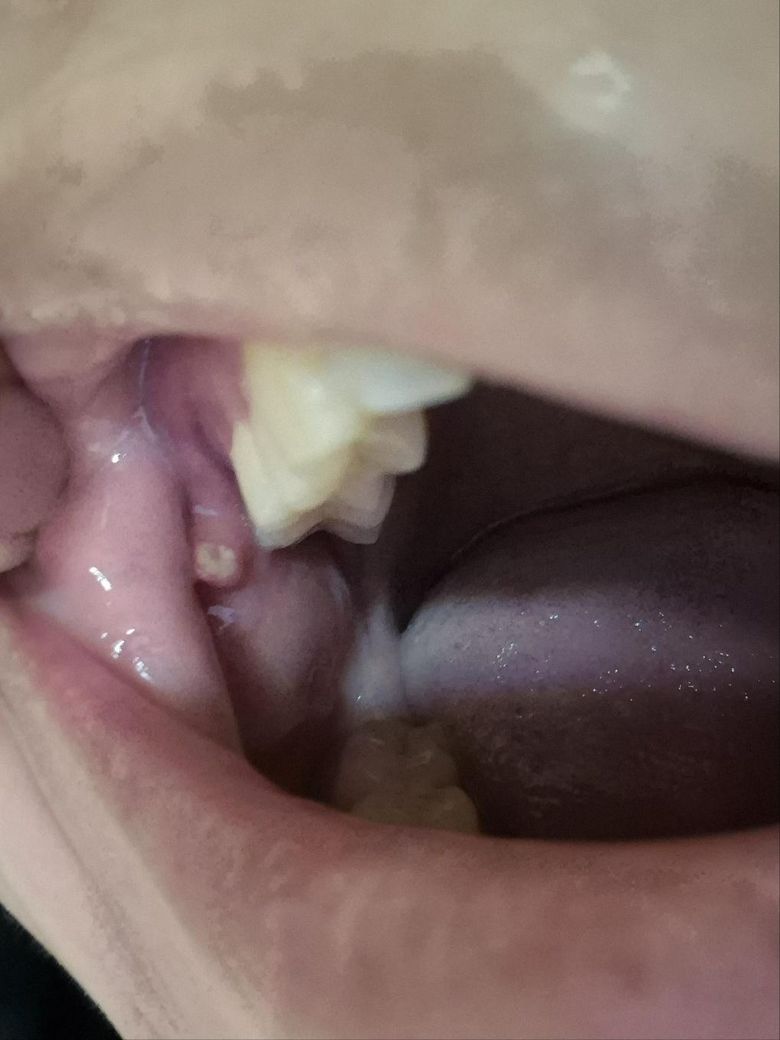

어금니 뒤쪽 잇몸 근처에 작은 혹 같은 게 보입니다

일주일정도 지낫는데, 크기가 작아지거나 호전되는거 없이 그대로 있습니다.

혀로 건드리면 조금 얼얼한데, 병원에 가서 떼어내야 하나요?

• 1번 째 사진

볼살이 치아에 씹혀서 생긴거 같습니다. 큰 문제가 잇는건 아니니 너무 걱정하지 않으셔도 될것같습니다.

사진으로 봤을 경우에는 구강 내 연조직이 내부 자극으로 인해서 기후화되고 구내염이 생긴 것으로 보입니다. 치아나 그 외에 어떤 구조물이 해당 부위를 자극하고 있지 않은지 확인해 보는 것이 좋으며 자극을 하는 부위가 있다면 다듬어 준다면 문제가 해결될 수 있습니다.

자세한 확인을 위해서 치과에서 진료를 받아보는 것을 권유드립니다.

일주일 정도 지났음에도 크기가 작아지지 않고 호전되지 않는다면 치과 가보시는 게 좋겠습니다.

대학병원 구강내과 가보시고 조직검사해보시기 바랍니다 검사 후 별다른 이상 없으면 제거해주면 됩니다